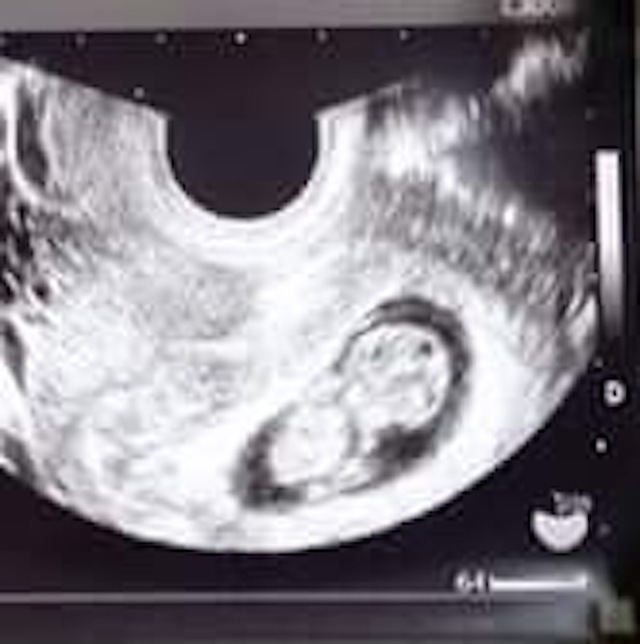

9週0日(9w0d・男の子・双子)|なおねこ さん(29歳)

エコー写真撮影時のエピソード:

妊娠9週目で双子と明らかに分かった写真です。

双子が欲しいと思っていたのでとてもびっくりしたし、初めての妊娠でびっくりと不安が入り混じった心境でした。また、病院も紹介された大学病院での初診だったのでとても緊張しました。